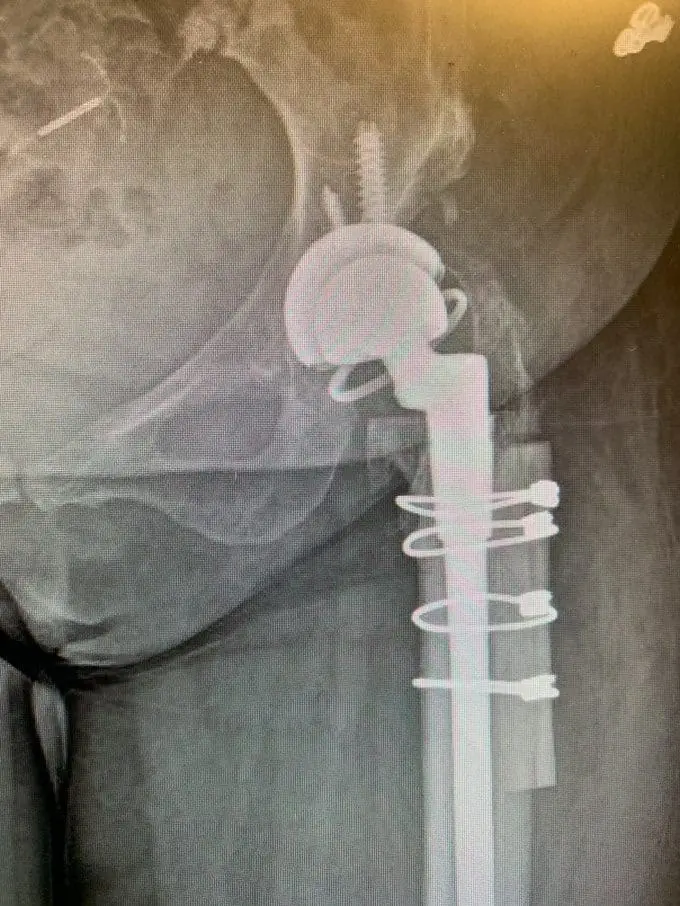

A lateral approach to the hip was used, and despite the patients’ abnormal anatomy, exposure of the hip was gained and the broad, shallow acetabulum was identified. The true acetabulum was identified, and the acetabular component was reamed for and placed without event, augmenting fixation with screws.

Accessing the femoral canal proved challenging, the femoral component was prepared. A femoral shortening osteotomy was then performed removing a significant amount of bone to allow for the hip to be relocated without excessive force.

Once this was completed, the definitive femoral component was placed, the osteotomy was fixed and held together with the removed bone acting as autologous bone graft and the hip was relocated.